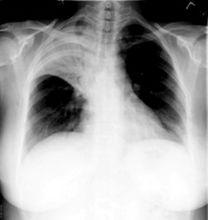

是影像學術語,空氣支氣管征:當實變擴展至肺門附近,較大的含氣支氣管與實變的肺組織形成對比,在實變區中可見到含氣的支氣管分支影,稱為支氣管氣像或空氣支氣管征。

是肺實變的重要徵象。

該徵象表明:(a)近側氣道通暢;(b)肺泡內的空氣經吸收(肺不張)或取代(肺炎),或兩者綜合而消失,在少見病例(如淋巴瘤)中空氣的消失是顯著的間質膨脹的結果。

空氣支氣管征常見於大葉性肺炎實變期。